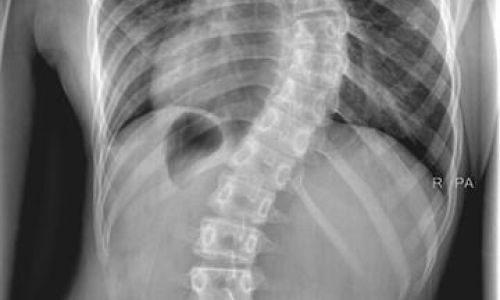

Σκολίωση

Είναι η πλάγια και στροφική απόκλιση μιας σειράς σπονδύλων από τη μέση ανατομική θέση του φυσιολογικού σπονδυλικού άξονα. Χαρακτηριστικά της είναι:

• ασυμμετρία μαστών και ώμων

• η έντονα λοξή πλάτη (±)

• δημιουργία πλευρικού ύβου (θωρακικά κυρτώματα)

• ασυμμετρία λεκάνης

Ανάλογα με την κλινική εικόνα η θεραπεία είναι είτε συντηρητική με κινησιοθεραπείες - φυσικοθεραπείες είτε η χρήση κηδεμόνα σε πιο σοβαρές περιπτώσεις.